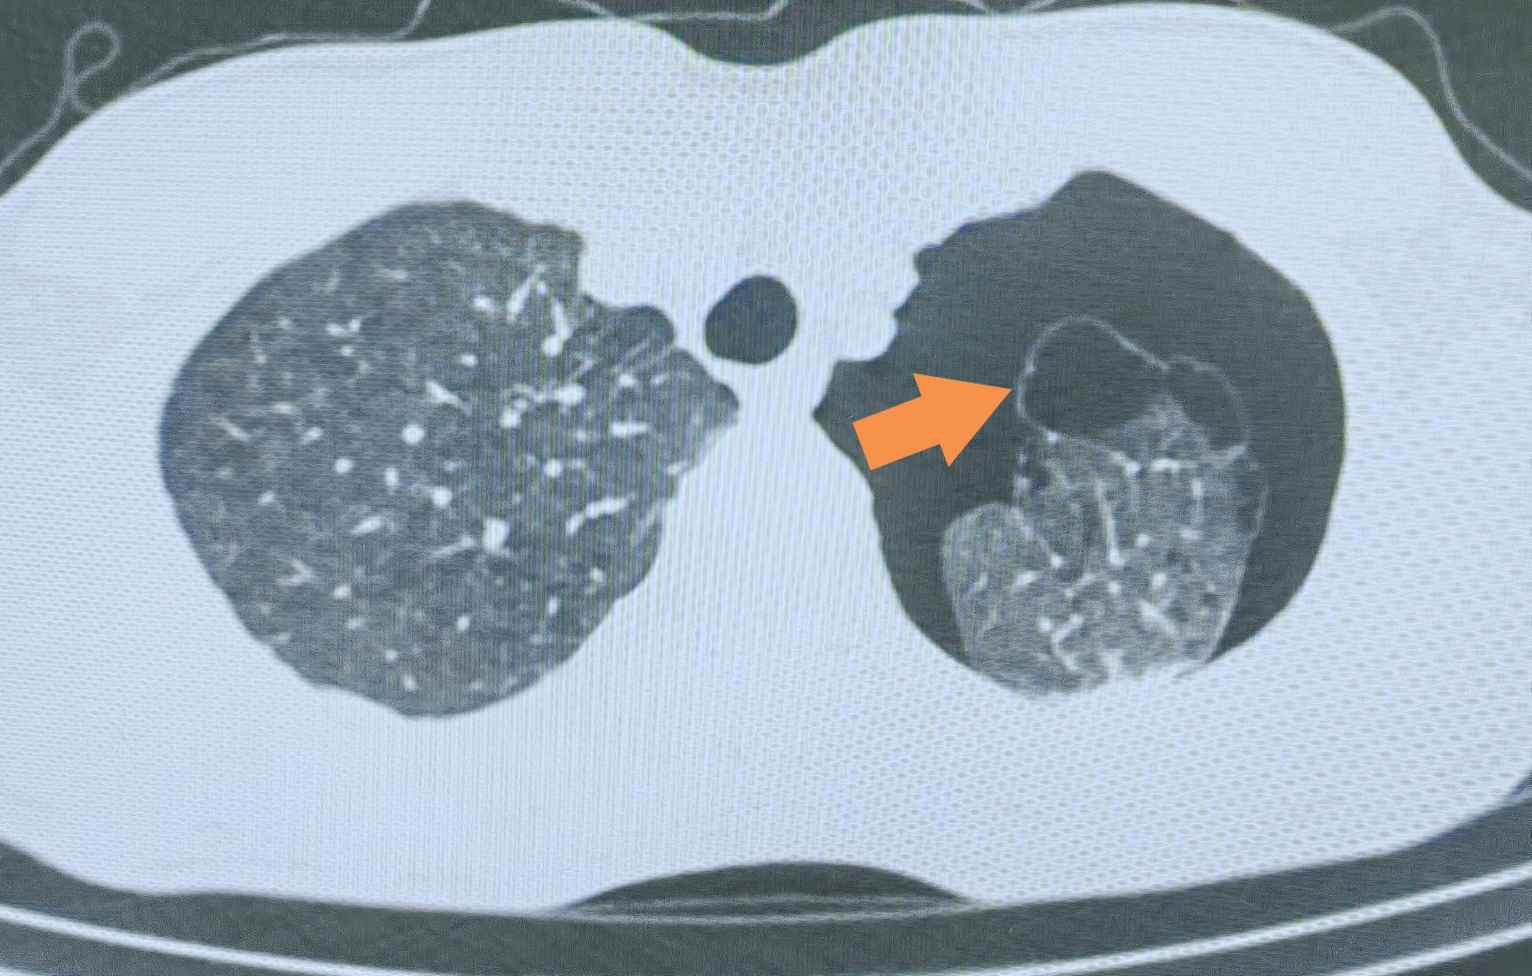

肺大疱(Pulmonary Bulla)通常是由于各种原因导致的肺泡壁破裂、融合,在肺组织内形成的直径超过1厘米的含气囊腔。

大多数肺大疱患者无明显症状,通常在体检时偶然发现。但如果肺大疱较大或破裂,可能出现:

气胸(突发胸痛、呼吸困难):肺大疱破裂后,空气进入胸腔,压迫肺部,导致呼吸不畅。